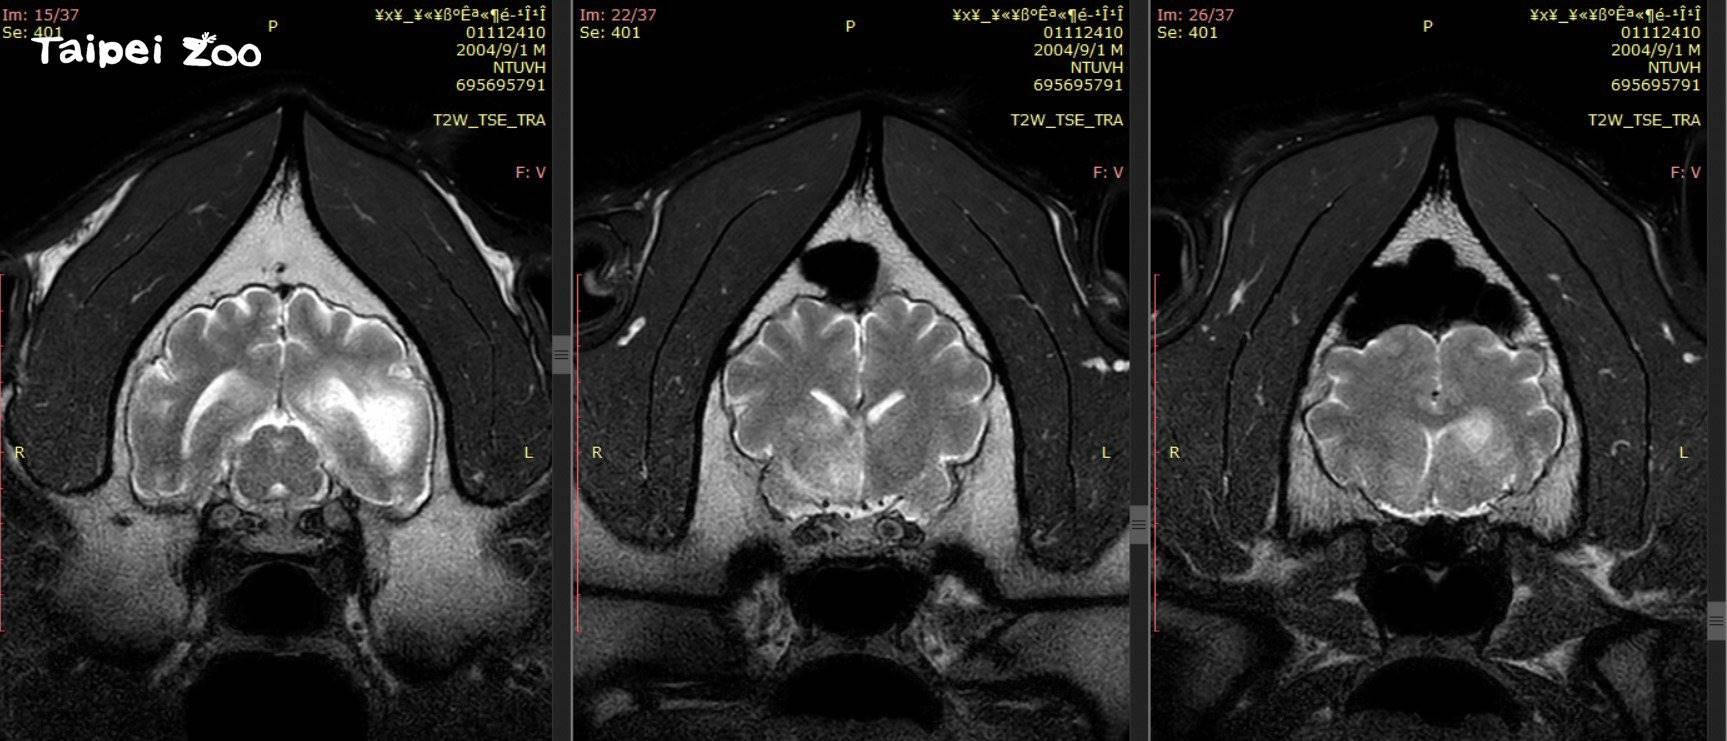

台灣大熊貓團團腦病變惡化,停止進行侵入性檢查。(臺北市立動物園Facebook圖片)

台灣雄性大熊貓「團團」的腦病變病況惡化,台北市立動物園公布「團團」的第2次磁力共振造影檢查結果,顯示「團團」腦部惡性腫瘤的機率大幅提高,由於未能進行腫瘤切片檢查,無法百分百確認,為維護動物福祉,會停止進行麻醉或侵入性檢查,改為採取舒緩照護方式。